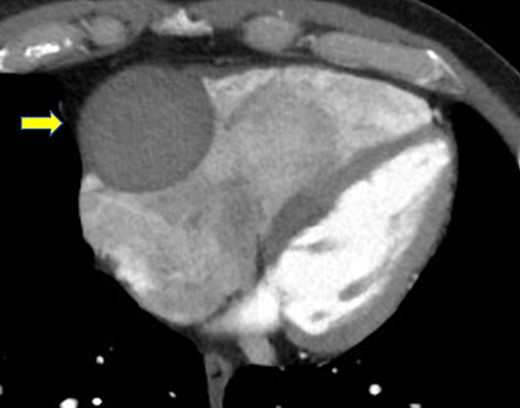

A 52-year-old man with transient ischemic attack was transferred to our hospital. He had a history of hypertension and dyslipidemia. He was conscious and had no particular symptoms after arriving at our hospital; however, an electrocardiogram showed ST-segment elevation in leads II, III, aVF, and V1–4. Enhanced computed tomography revealed a giant CAA at the RCA (Fig. 1). The aneurysm measured 50 mm in diameter and was completely occluded by a thrombus. Additionally, the coronary artery distal from the CAA did not show contrast. Emergency coronary angiography was performed. The RCA was occluded at segment #2 proximal to the CAA, and the CAA did not show contrast (Fig. 2A); however, the artery distal to the CAA showed contrast via a collateral artery from the left circumflex artery (Fig. 2B). Anticoagulation therapy involving intravenous heparin was started. After several hours, the ST-segment elevation disappeared quickly, and there were no particular symptoms. The creatine kinase level spiked to a maximum of 1475 IU/L, which then decreased to 432 IU/L on the next day. Four days after starting therapy, enhanced computed tomography and coronary angiography were performed again. They showed slight contrast in the CAA and the distal coronary artery (Fig. 3). Thus, surgery was performed to prevent the CAA from rupturing.

Enhanced computed tomography shows a giant coronary artery aneurysm (arrow) at the right coronary artery, which is occluded completely by a thrombus.